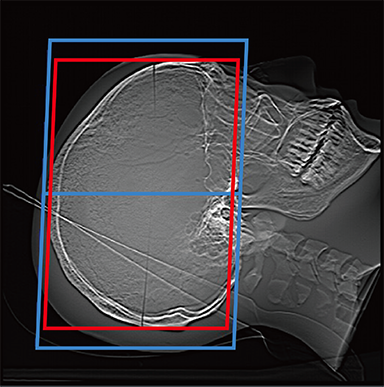

FCT iStream automatically*2 sets the scanning range using the scanogram image by AutoPose function. Since the margins can be set in advance, the range can be customized according to the preference of the facility. iTilt automatically creates and enables observation of tilted images during scanning.

When set to OM Line

Red: automatically set position, Blue: automatically set position + margin setting position